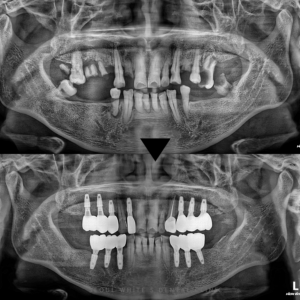

영도치과, 치주질환과 오래된 보철로 무너진 치아 전악 임플란트로!

영도치과, 치주질환과 오래된 보철로 무너진 치아 전악 임플란트로! 안녕하세요! 영도치과 서울화이트S치과 입니다! 이전에 치과에서 보철치료를 많이 하셨거나 단 한개라도 보철물 장착으로 마무리 하신 분들께 영도치과 서울화이트S치과에서 드리는 말씀이…